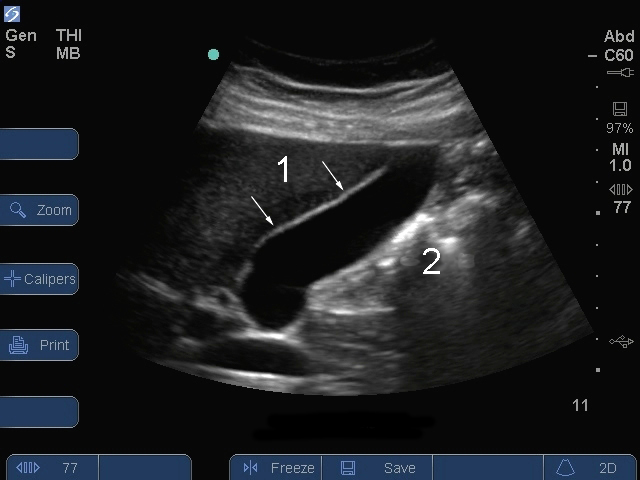

S シリーズ: 胆嚢縦断面2

前胆嚢壁

腸内ガス